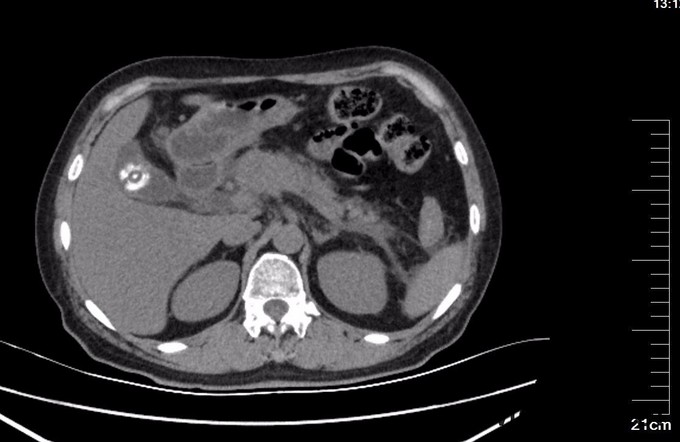

查体: 腹平坦,未见胃肠型及蠕动波,腹软,右上腹压痛明显,伴反跳痛,无肌紧张,肝脾肋下未扪及肿大,无移动性浊音,双肾区无叩痛,肠鸣音存在。 辅查:超声检查: 胆囊大小约6.1x2.4cm,壁厚约0.3cm,囊内见多个强回声团,较大者直径约0.9cm,声影(+),移动(+)。 胰腺轮廓模糊,胰腺头、体厚度分别为2.4cm、2.6cm,回声粗糙,主胰管直径约0.1cm。胰尾部受肠气干扰显示不清。 腹腔未见明显积液影像。 CT提示:肝内外胆管未见明显扩张,胆囊壁稍厚,内见结节状高密度影,直径约1.9cm。胆总管下段细点状高密度影,大小约0.2cm,胰腺边界模糊,周围多发条状絮状渗出影,双肾前筋膜增厚,十二指肠管壁模糊。血淀粉酶(AMY)、血脂肪酶(LPS )及尿淀粉酶(Amy-U)明显增高(见图里化验报告)。

诊断: 胆囊结石 胆总管结石 胆源性胰腺炎 治疗:胃肠减压,抗炎,补液,抑酶,抑酸治疗,急诊内镜至十二指肠,见十二指肠乳头肿胀,选择性胆管插管顺利,造影见胆总管直径12mm,末段可见数处充盈缺损,最大大小约6mm,行乳头肌切开(EPT),以12mm球囊扩张乳头(1ATM,40s)后,取石球囊取出黄色结石1枚及少许泥沙样结石,球囊及盐水清理胆道,再次造影见胆总管内无充盈缺损,留置鼻胆引流管,选择性胰管插管顺利,留置5Fr5cm胰管塑料支架一枚。次日,患者血淀粉酶恢复正常,血脂肪酶降至156U/L,腹痛明显缓解。EPT第二日,全麻下腹腔镜胆囊切除术(LC),手术顺利,术中发现胰腺无坏死,未处理胰腺,LC术后2天再次经EPT留置的ENBD管造影,未发现胆总管结石,复查血淀粉酶及脂肪酶,均恢复正常,拔管出院。